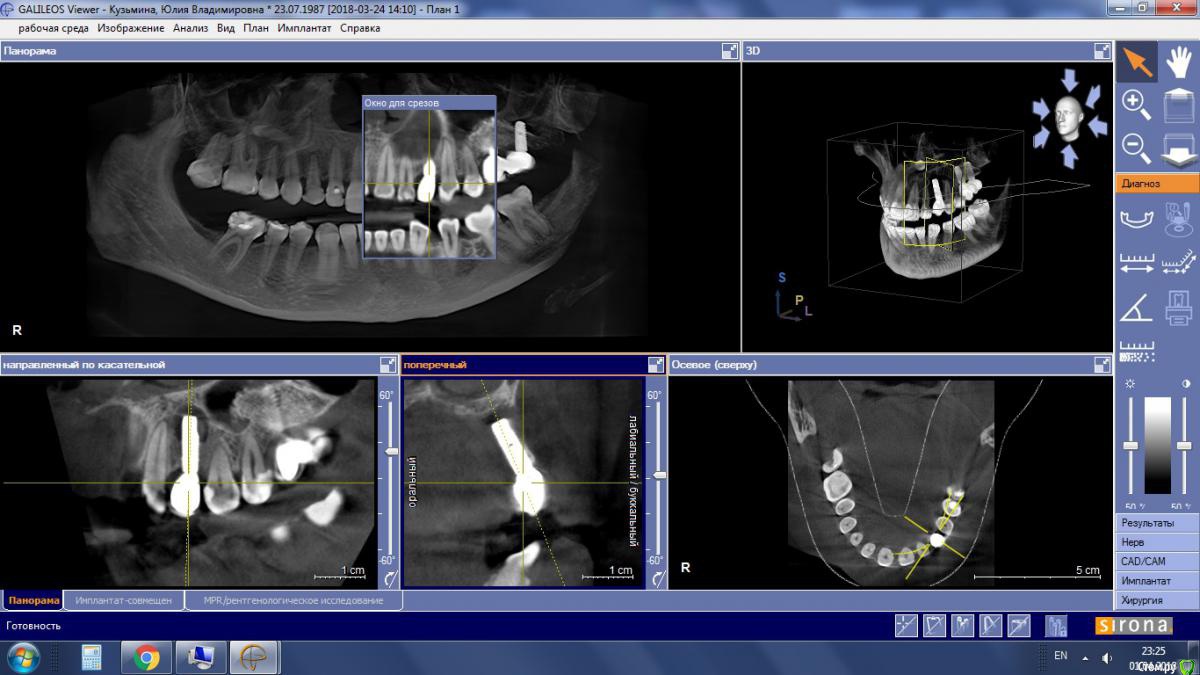

Ю.Ягн Опубликовано 30 марта, 2018 Автор Поделиться Опубликовано 30 марта, 2018 (изменено) Имплантолог предполагал, что инфекция пошла от двойки, но связи не было обнаружено.Мне 30 лет2ое детейработаникаких серьезных хронических заболеванийВ декабре болела ангиной (очень тяжело - 2 курса антибиотиков), а феврале ОРВИ. тоже тяжело 6 дней т. 39. 5 потом бронхит и антибиотики.Стала чихать более сказать нечего. Имплантант ставили сразу после удаления шатающегося молочного зуба в 15 году, сейчас имплантант неподвиженКТкт 24.03.2018 юля орто.7z http://fayloobmennik.cloud/7235123 Изменено 30 марта, 2018 пользователем Ю.Ягн Ссылка на комментарий

колесников Опубликовано 31 марта, 2018 Поделиться Опубликовано 31 марта, 2018 Возможно просто длинный имплант,надо кт посмотреть Ссылка на комментарий

колесников Опубликовано 1 апреля, 2018 Поделиться Опубликовано 1 апреля, 2018 Вы разместили не кт,а панорамный снимок сделаный на 3д томографе. Ссылка на комментарий

колесников Опубликовано 1 апреля, 2018 Поделиться Опубликовано 1 апреля, 2018 Там в описании даже значится ОРТО. Это панорамный снимок,не кт Ссылка на комментарий

Ю.Ягн Опубликовано 1 апреля, 2018 Автор Поделиться Опубликовано 1 апреля, 2018 Там в описании даже значится ОРТО. Это панорамный снимок,не ктНо там же в начале написано КТ? Да я не должна была писать ОРТО, но мне так понятнее. Там КТ! Ссылка на комментарий